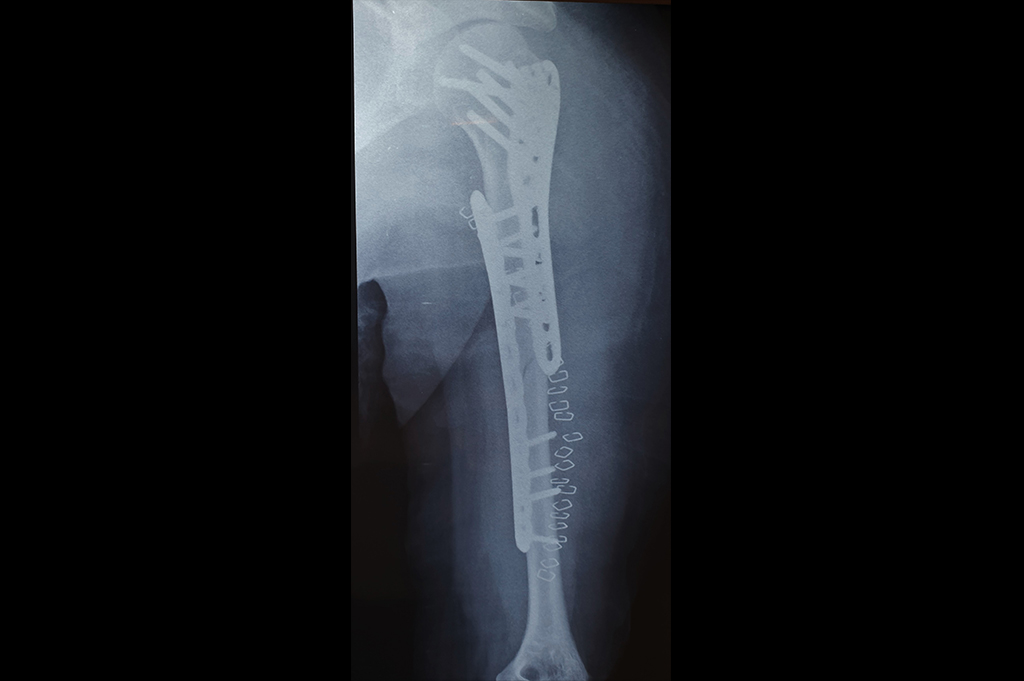

Humerus